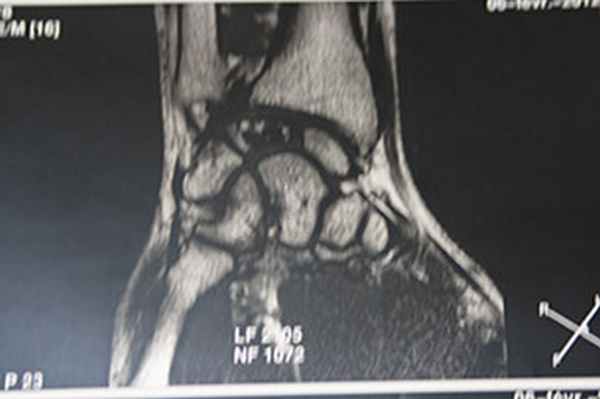

Некроз полулунной кости на МРТ

Большинство пациентов жалуются на боль запястье, усиливающуюся при нагрузке. При осмотре определяется болезненность в проекции полулунной кости. Первые шаги для диагностики болезни Кинбека — это сбор анамнеза, осмотр и рентгенограммы. Иногда требуются дополнительные исследования, наиболее информативным из которых является магнитно-резонансная томография. Именно МРТ позволяет выявить нарушение кровоснабжения полулунной кости, когда еще нет изменений на рентгенограммах. Также могут применяться компьютерная томография или остеосцинтиграфия.

МРТ при болезни Кинбека.